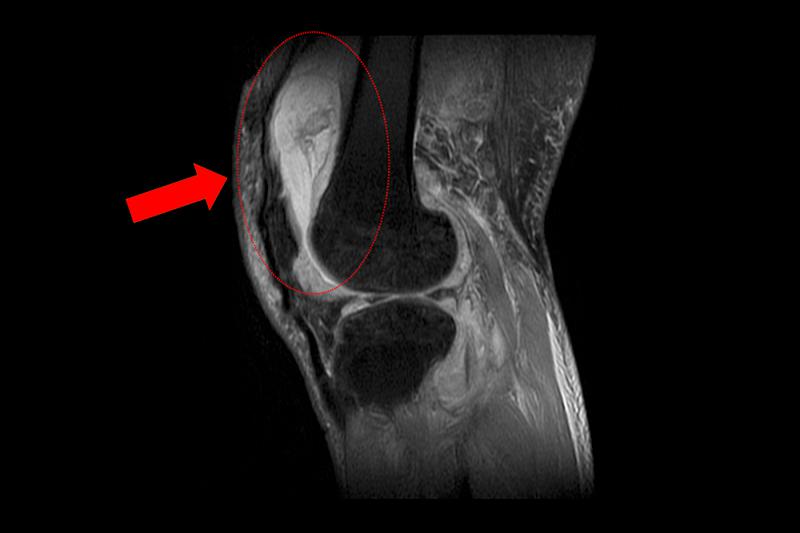

賴先生長期左膝腫痛、幾乎無法行走,就診時表示以為只是退化性關節炎,服用止痛藥、抽關節積水、熱敷復健數月卻越來越嚴重,來院時膝蓋已腫脹無法彎曲。關節中心主任周立展抽取膝關節液化驗後發現,白血球數值雖偏高,但並非典型的細菌感染,懷疑有其他原因。周主任安排病人住院,進一步X光與磁振造影檢查,顯示膝蓋內已有大量積液並化膿,屬於嚴重關節感染。

周立展主任避免病人感染惡化,緊急施行微創關節鏡清創手術,檢體送病理化驗後竟發現結核分枝桿菌,顯示並非單純膝蓋退化。周主任會診感染科與胸腔科醫師共同診斷,在病人痰液培養出結核菌,證實為「肺結核合併肺外感染」。結核菌最初在肺部引起感染,再經由血液或淋巴傳播,最後侵犯膝關節。病人住院期間接受抗結核藥物治療,一周後膝蓋腫脹消退,可正常彎曲行走;出院後仍須持續服藥至少九個月,並定期門診追蹤,確保結核菌完全清除。